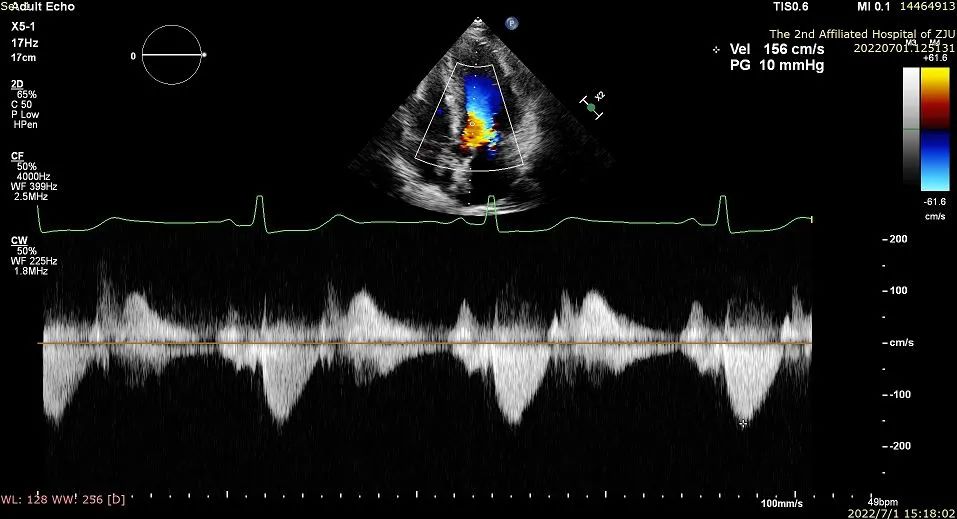

2022年7月1日在浙江大学医学院附属第二医院导管室,应用Liwen RF射频消融系统经心尖到达肥厚室间隔进行射频消融,术后即刻超声显示靶区消融充分,术后即可左室流出道压差显著降低。

术后左室流出道压差